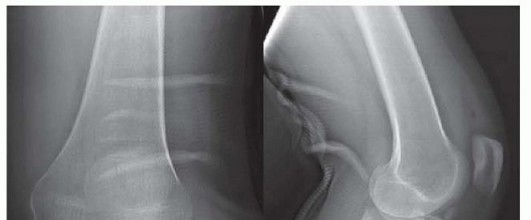

DEFINITION Fracture of the olecranon process is common, usually displaced, and nearly always treated operativ…